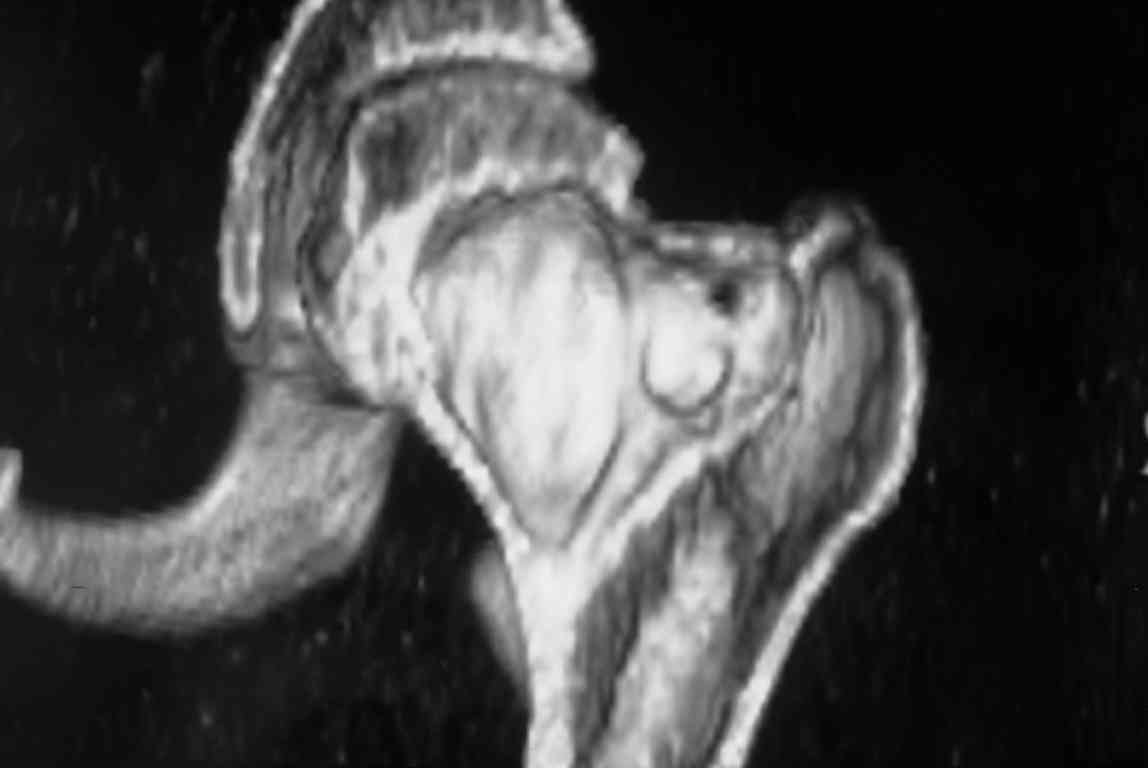

Больная Л., 23 года.

Из анамнеза:со слов больной в 2006 г. появились боли правой н/конечности, обратилась поместу жительства к хирургу, было выполнена МРТ поясничного отдела позвоночника,назначено физиолечение.

Через 2 месяца боли прекратились, через 4 месяца рецидив болевого синдрома. С 2006 – 2010 проводилось консервативное лечение по поводу остеохондроза поясничного отдела позвоночника. В октябре 2010 г. боли усилились. Выполнены Ro и КТ правого тазобедренного сустава, выявлен очаг патологической перестройки. Была направлена на консультацию в УНИИТО.

В УНИИТО виюне 2011 г. поставлен дифференциальный диагноз между фибромой, солитарной костнойкистой и гигантоклеточной опухолью.